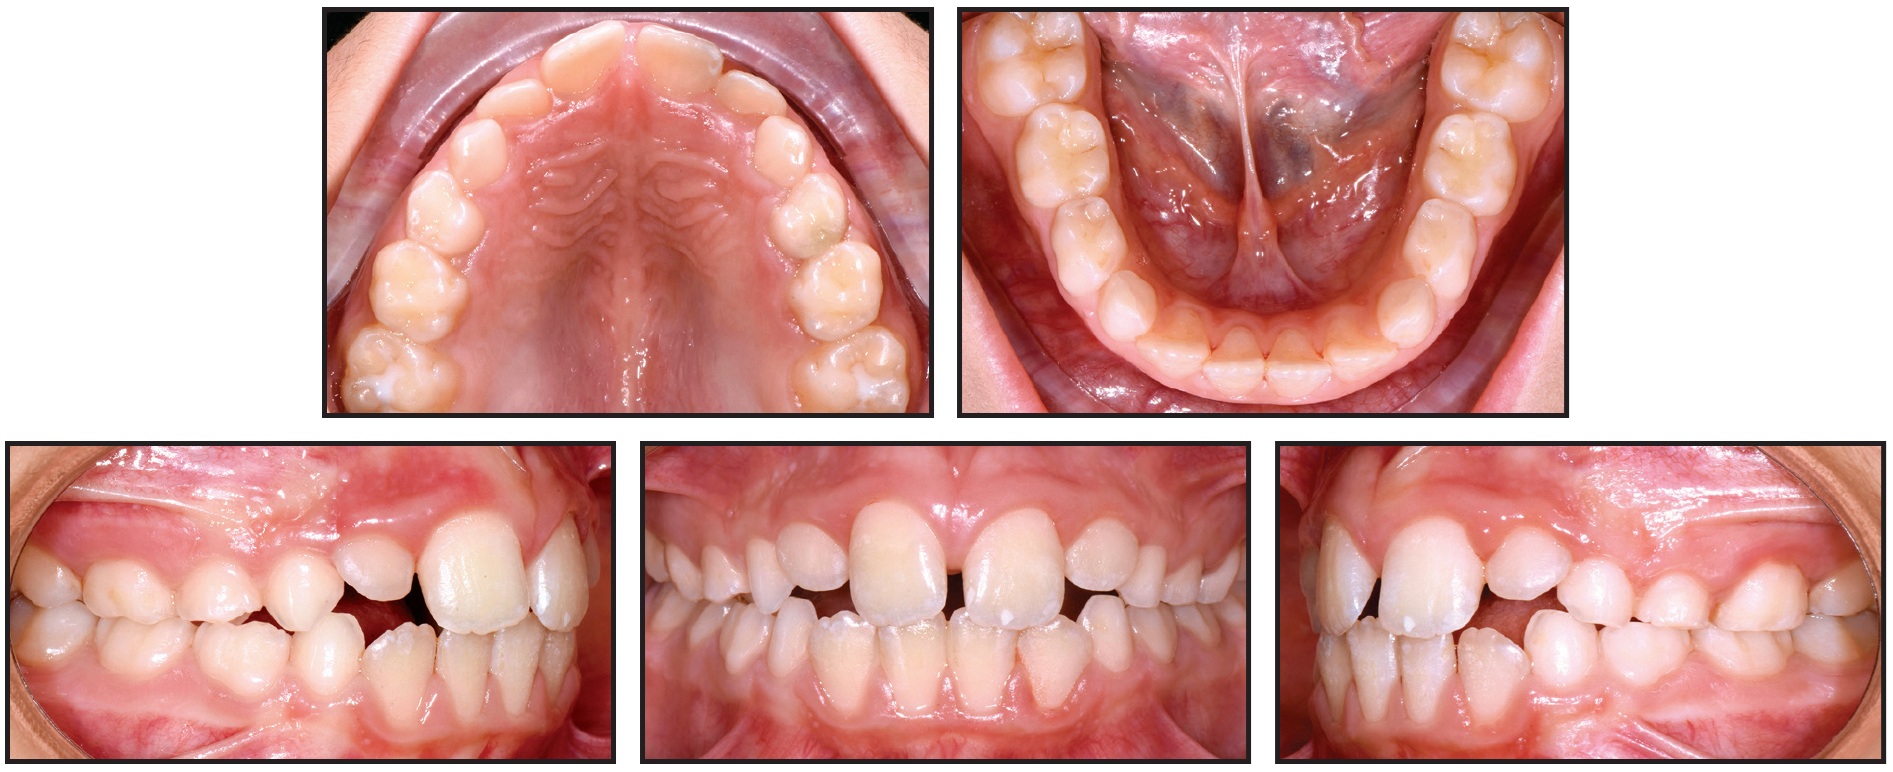

A 6-year-old male in the mixed dentition presented with a lack of space for his lateral incisors and a crossbite associated with a lateral mandibular shift to the right and a transverse discrepancy (Fig. 3, Table 1). The upper right central incisor had been extracted following an intrusive trauma at age 4; the space had been maintained with a transpalatal arch and composite pontic.

Fig. 7 Case 2. A. 6-year-old female patient with maxillary transverse deficiency and bilateral crossbite before treatment (continued in next image).